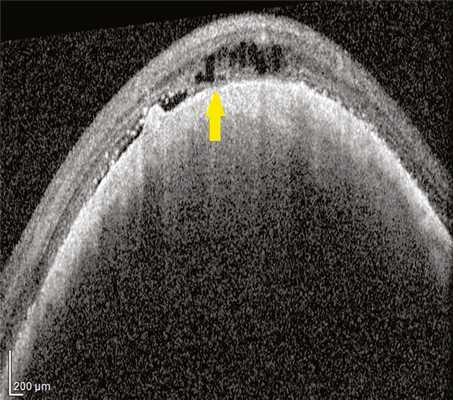

По результатам ОКТ-исследования в 49 глазах из 64 выявлены признаки нарушения дифференцировки комплекса хориоидея/МБ/РПЭ. Статистически достоверных различий размеров МХ при отсутствии или наличии прорастания ее в сетчатку выявлено не было (р=0,83 и р=0,23 соответственно для проминенции и диаметра). Разрушение сетчатки опухолью всегда начиналось с разрушения МБ и РПЭ, что мы наблюдали в 73% случаев при толщине опухоли от 1 мм. Единый конгломерат сетчатка/опухоль на большом протяжении отмечен в 21 (31,34%) глазу при средней толщине МХ — 3,0±0,29 мм, среднем диаметре — 10,29±0,72 мм. Изменения на ОКТ-сканах были представлены протяженной гиперрефлективной полосой с интенсивно гиперрефлективным подлежащим комплексом опухоли и нарушением дифференцировки надлежащей сетчатки, в первую очередь ее наружных слоев (рис. 1). Рис. 1. Горизонтальный ОКТ-скан через МХ (проминенция 3,0 мм). Стрелками указана зона протяженного дефекта МБ.

В 15 (22,4%) глазах визуализированы зоны разрыва МБ и РПЭ, нарушение дифференцировки структуры хориоидеи и сетчатки при средней проминенции МХ — 2,76±0,23 мм, среднем диаметре — 9,1±0,52. В этих глазах на ОКТ-сканограммах в зоне опухоли МБ была представлена в виде тонкой интенсивно гиперрефлективной линии на границе опухолевого комплекса и сетчатки. На протяжении этой линии имелись локальные дефекты с изменениями, аналогичными описанным выше (рис. 2). Рис. 2. Горизонтальный ОКТ-скан через МХ (проминенция 2,9 мм). Стрелкой указан локальный дефект МБ.